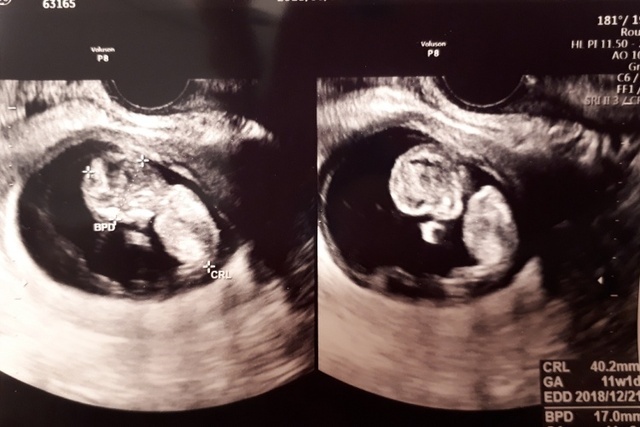

11週2日(11w2d・男の子)|だみだみ13 さん(32歳)

エコー写真撮影時のエピソード:

健診後に、実家の母へ、何気なく写真を送り、報告しました。見た母は、「どこがどのパーツか分からない。」と言うので、分かりやすいと思うけどなぁと思いながら説明すると、「さすがあんたの子。首が長い!」と言われてました。

自分では気付かないところを見てくれていました。

実際産まれて、未だに子どもの首が長いとは思いませんが、今後が楽しみです。